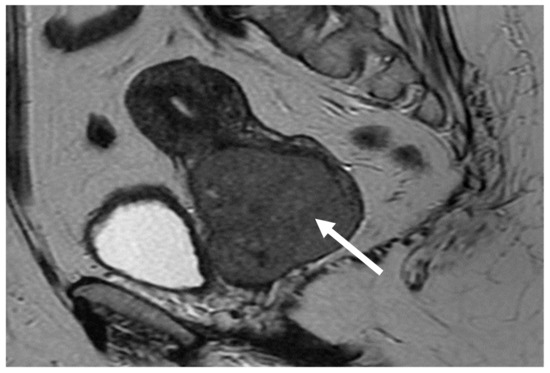

| 11. Weiyan Zhou [18] | 2016 | 1/31 | − | (DLBCL) | 6 × R-CHOP | 12 months/PET-CT/MRI |